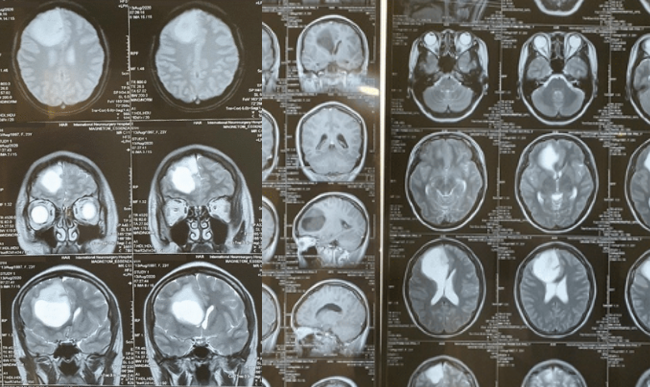

Đau đầu kèm mờ mắt nhanh ở một bệnh nhân nữ trong 07 ngày. Được chẩn đoán U nào thùy trán